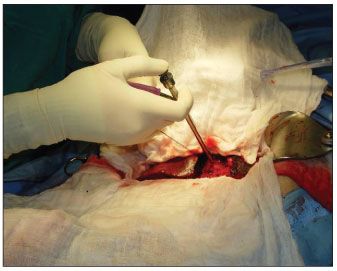

Figure 4 – A purse-string suture is placed in the wall of the large echinococcal cyst in the left lobe of the liver to control potential spillage of cyst contents.

Therapy with oral albendazole 400 mg twice daily was initiated on admission. Ten days later, the patient underwent an exploratory laparotomy with cholecystectomy and partial hepatic lobe resection (Figure 4). Hypertonic saline solution (15%) was instilled in the liver cysts (Figure 5), and they were decompressed, evacuated (Figure 6), and marsupialized.